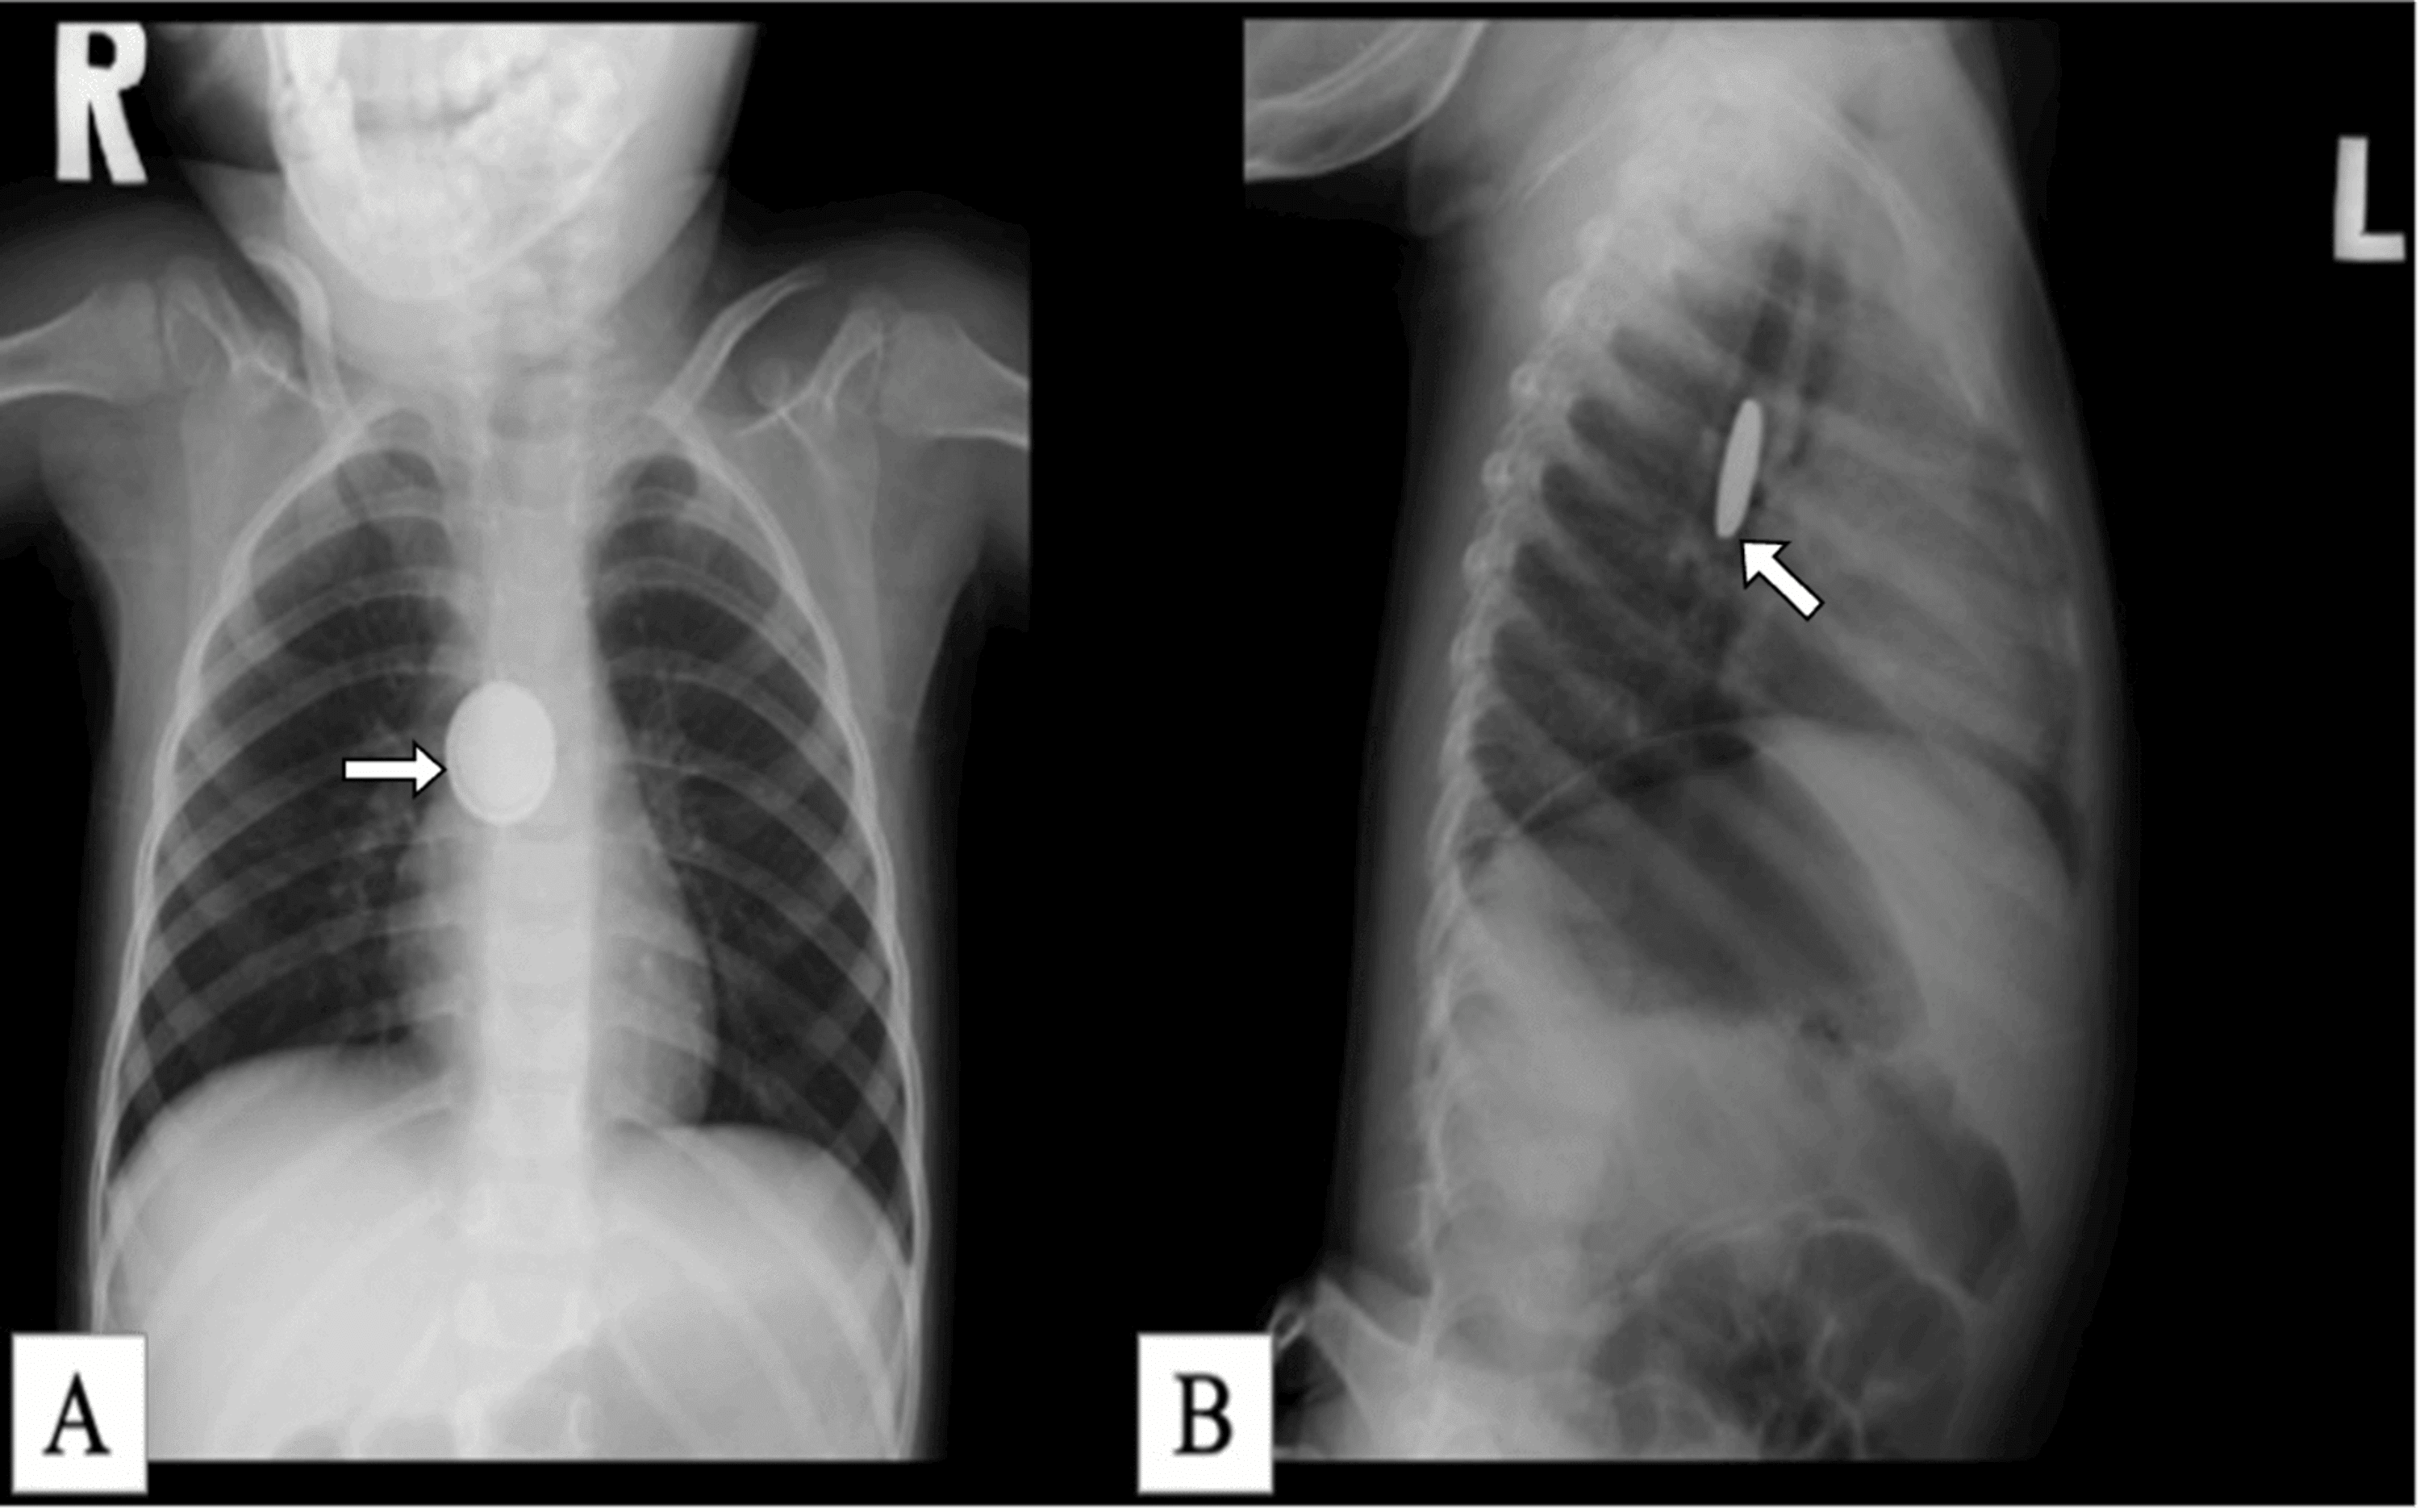

HALO sign on plain radiography suggests ingestion of this

What is a button battery ingestion?

These items must be removed via emergent endoscopy

What are button batteries in the esophagus, double magnets, sharp objects, objects >5cm long and >2cm wide